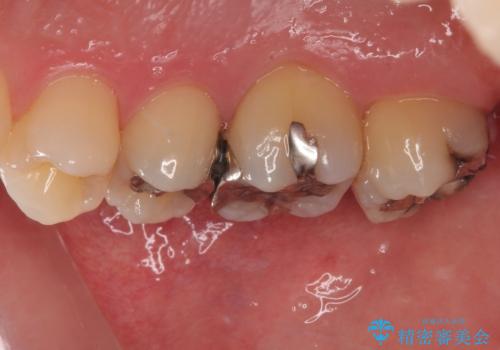

矯正治療により処置が可能な位置に歯が移動したため、オールセラミッククラウンにて補綴治療を行うこととしました。

歯列が移動したとはいえ、左右ともに後方傾斜しており、むし歯の除去、形成(形を整える)、型取りの全てが非常に困難な処置となりました。

セラミッククラウンの適合はレントゲン写真からも分かる通り、境界がぴったりと合った、高適合のものとなりました。